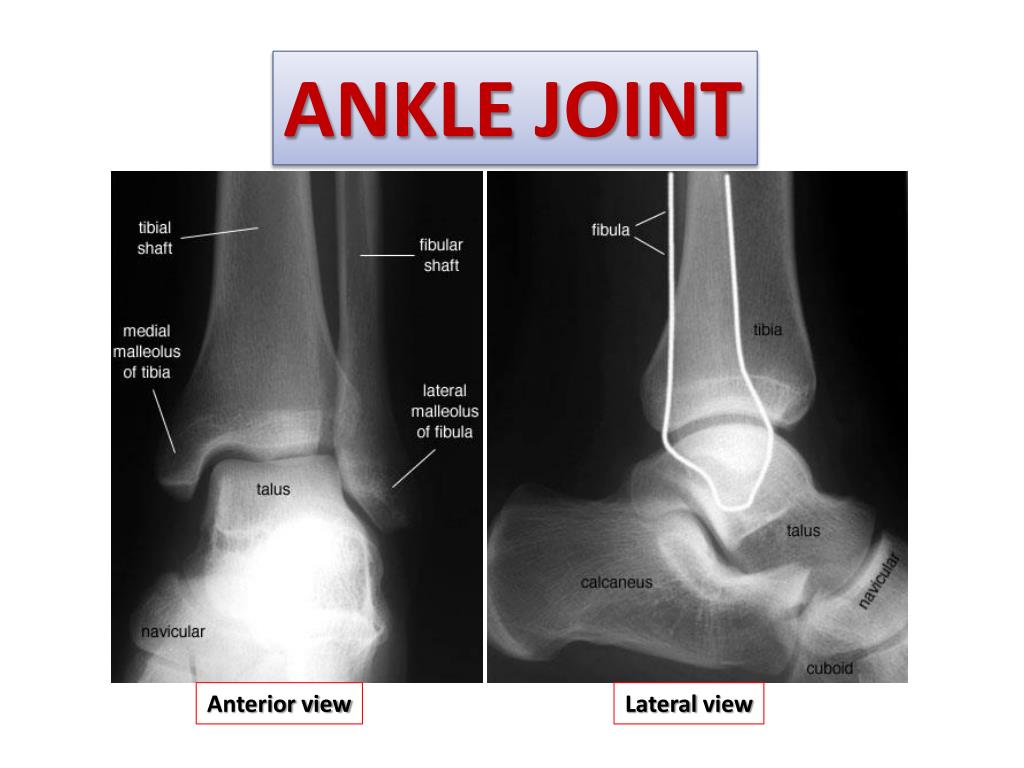

19. ANKLE JOINT Anterior view Lateral view

20. Type & Articular Surfaces TYPE: synovial, hinge joint. • ARTICULAR SURFACES: UPPER: • A socket formed by: Lateral malleolus. the lower end of tibia & medial malleolus. LOWER: • Body of talus.